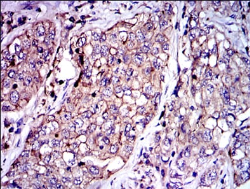

SERPINE1 Mouse Monoclonal antibody[1D5H9]

IHC    1/200 - 1/1000